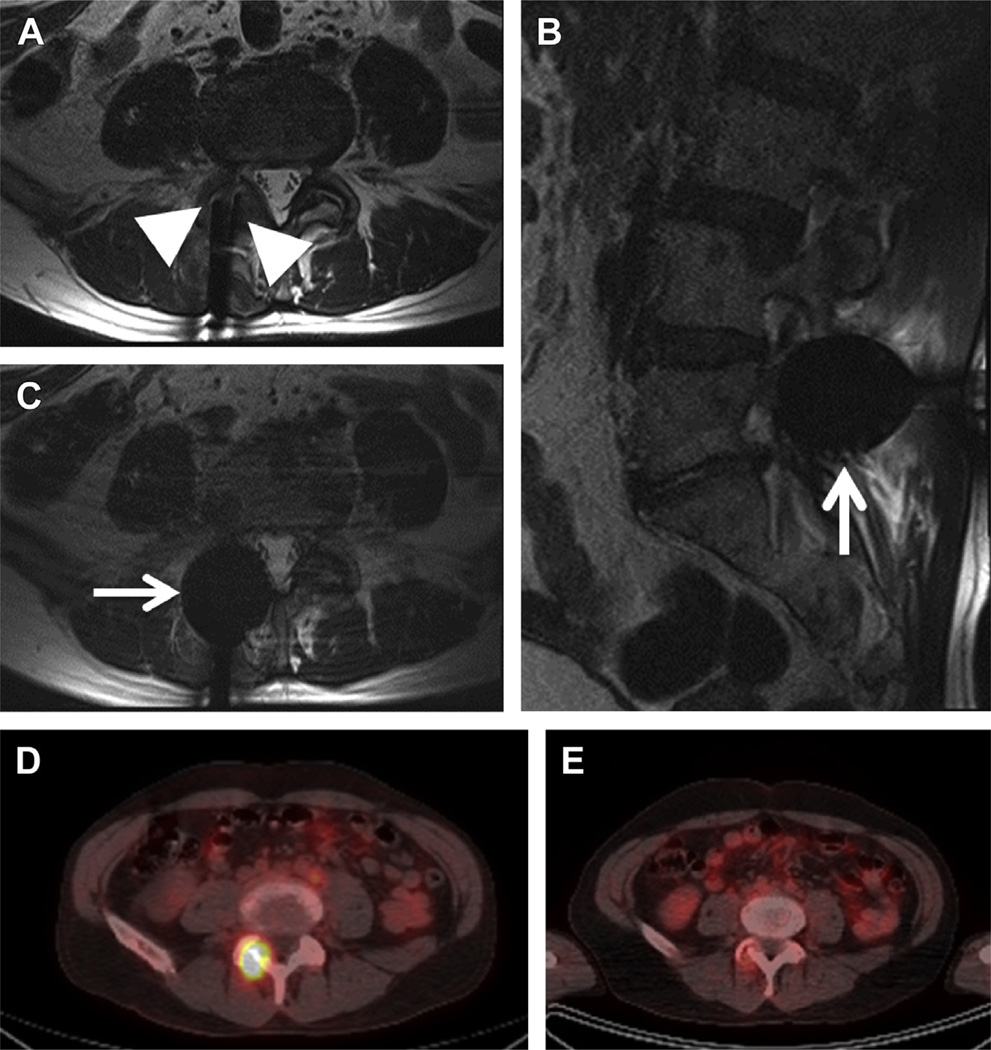

A 68-year-old man with a history of metastatic prostate cancer and diffuse large B-cell lymphoma was found to have a new mass eroding the right L4 lamina and right L4–L5 facet joint. To prevent spinal canal compromise and instability at this level, MR imaging–guided cryoablation was considered the most appropriate treatment in this nonsurgical candidate.

Using MR imaging guidance (Fig. 6), two 17-gauge cryoprobes were placed into either side of the mass. With frequent MR imaging monitoring, using turbo spin echo T2-weighted sequences to ensure the iceballs encompassed the mass but did not involve the CSF, alternating cycles of freezing and thawing were performed as follows: 15-minute freeze, followed by 10-minute passive thawing, followed by 15-minute freeze, then 3-minute active thawing. The second cycle of freezing was performed at 100%, then decreased to 40% at 7 minutes, then 20% at 10 minutes. Following the active thaw, the cryoprobes were removed without complication. On subsequent follow-up, the patient reported improvement in his pain without evidence of complication. The subsequent follow-up PET/CT studies showed there was complete resolution of fluorodeoxyglucose activity of the lesion and no further thinning of the lamina or epidural extension.

Fig. 6.

Cryoablation of metastatic spinal disease. Axial turbo spin echo T2-weighted sequence (A) shows the placement of two cryoprobes (arrowheads) at either side of the lesion at the right L4 lamina bordering the right L4–L5 facet joint. During a maximal freeze period, the iceball (arrows) can be seen in relation to the surrounding structures and adjacent CSF and cauda equina nerve roots (B, C), ensuring coverage of the lesion without subsequent freezing of these adjacent structures. Fused axial image of the PET-CT study before the cryoablation (D) shows the lesion to be highly fluorodeoxyglucose avid, with follow-up PET 6 months following the procedure (E) showing near complete resolution of the fluorodeoxyglucose avidity at the treatment site.